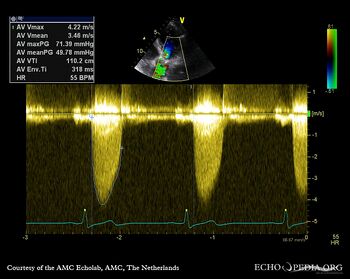

E00862.gif E00863.gif

PSAX: severe aortic valve stenosis A5CH with Color: mild aortic regurgitation